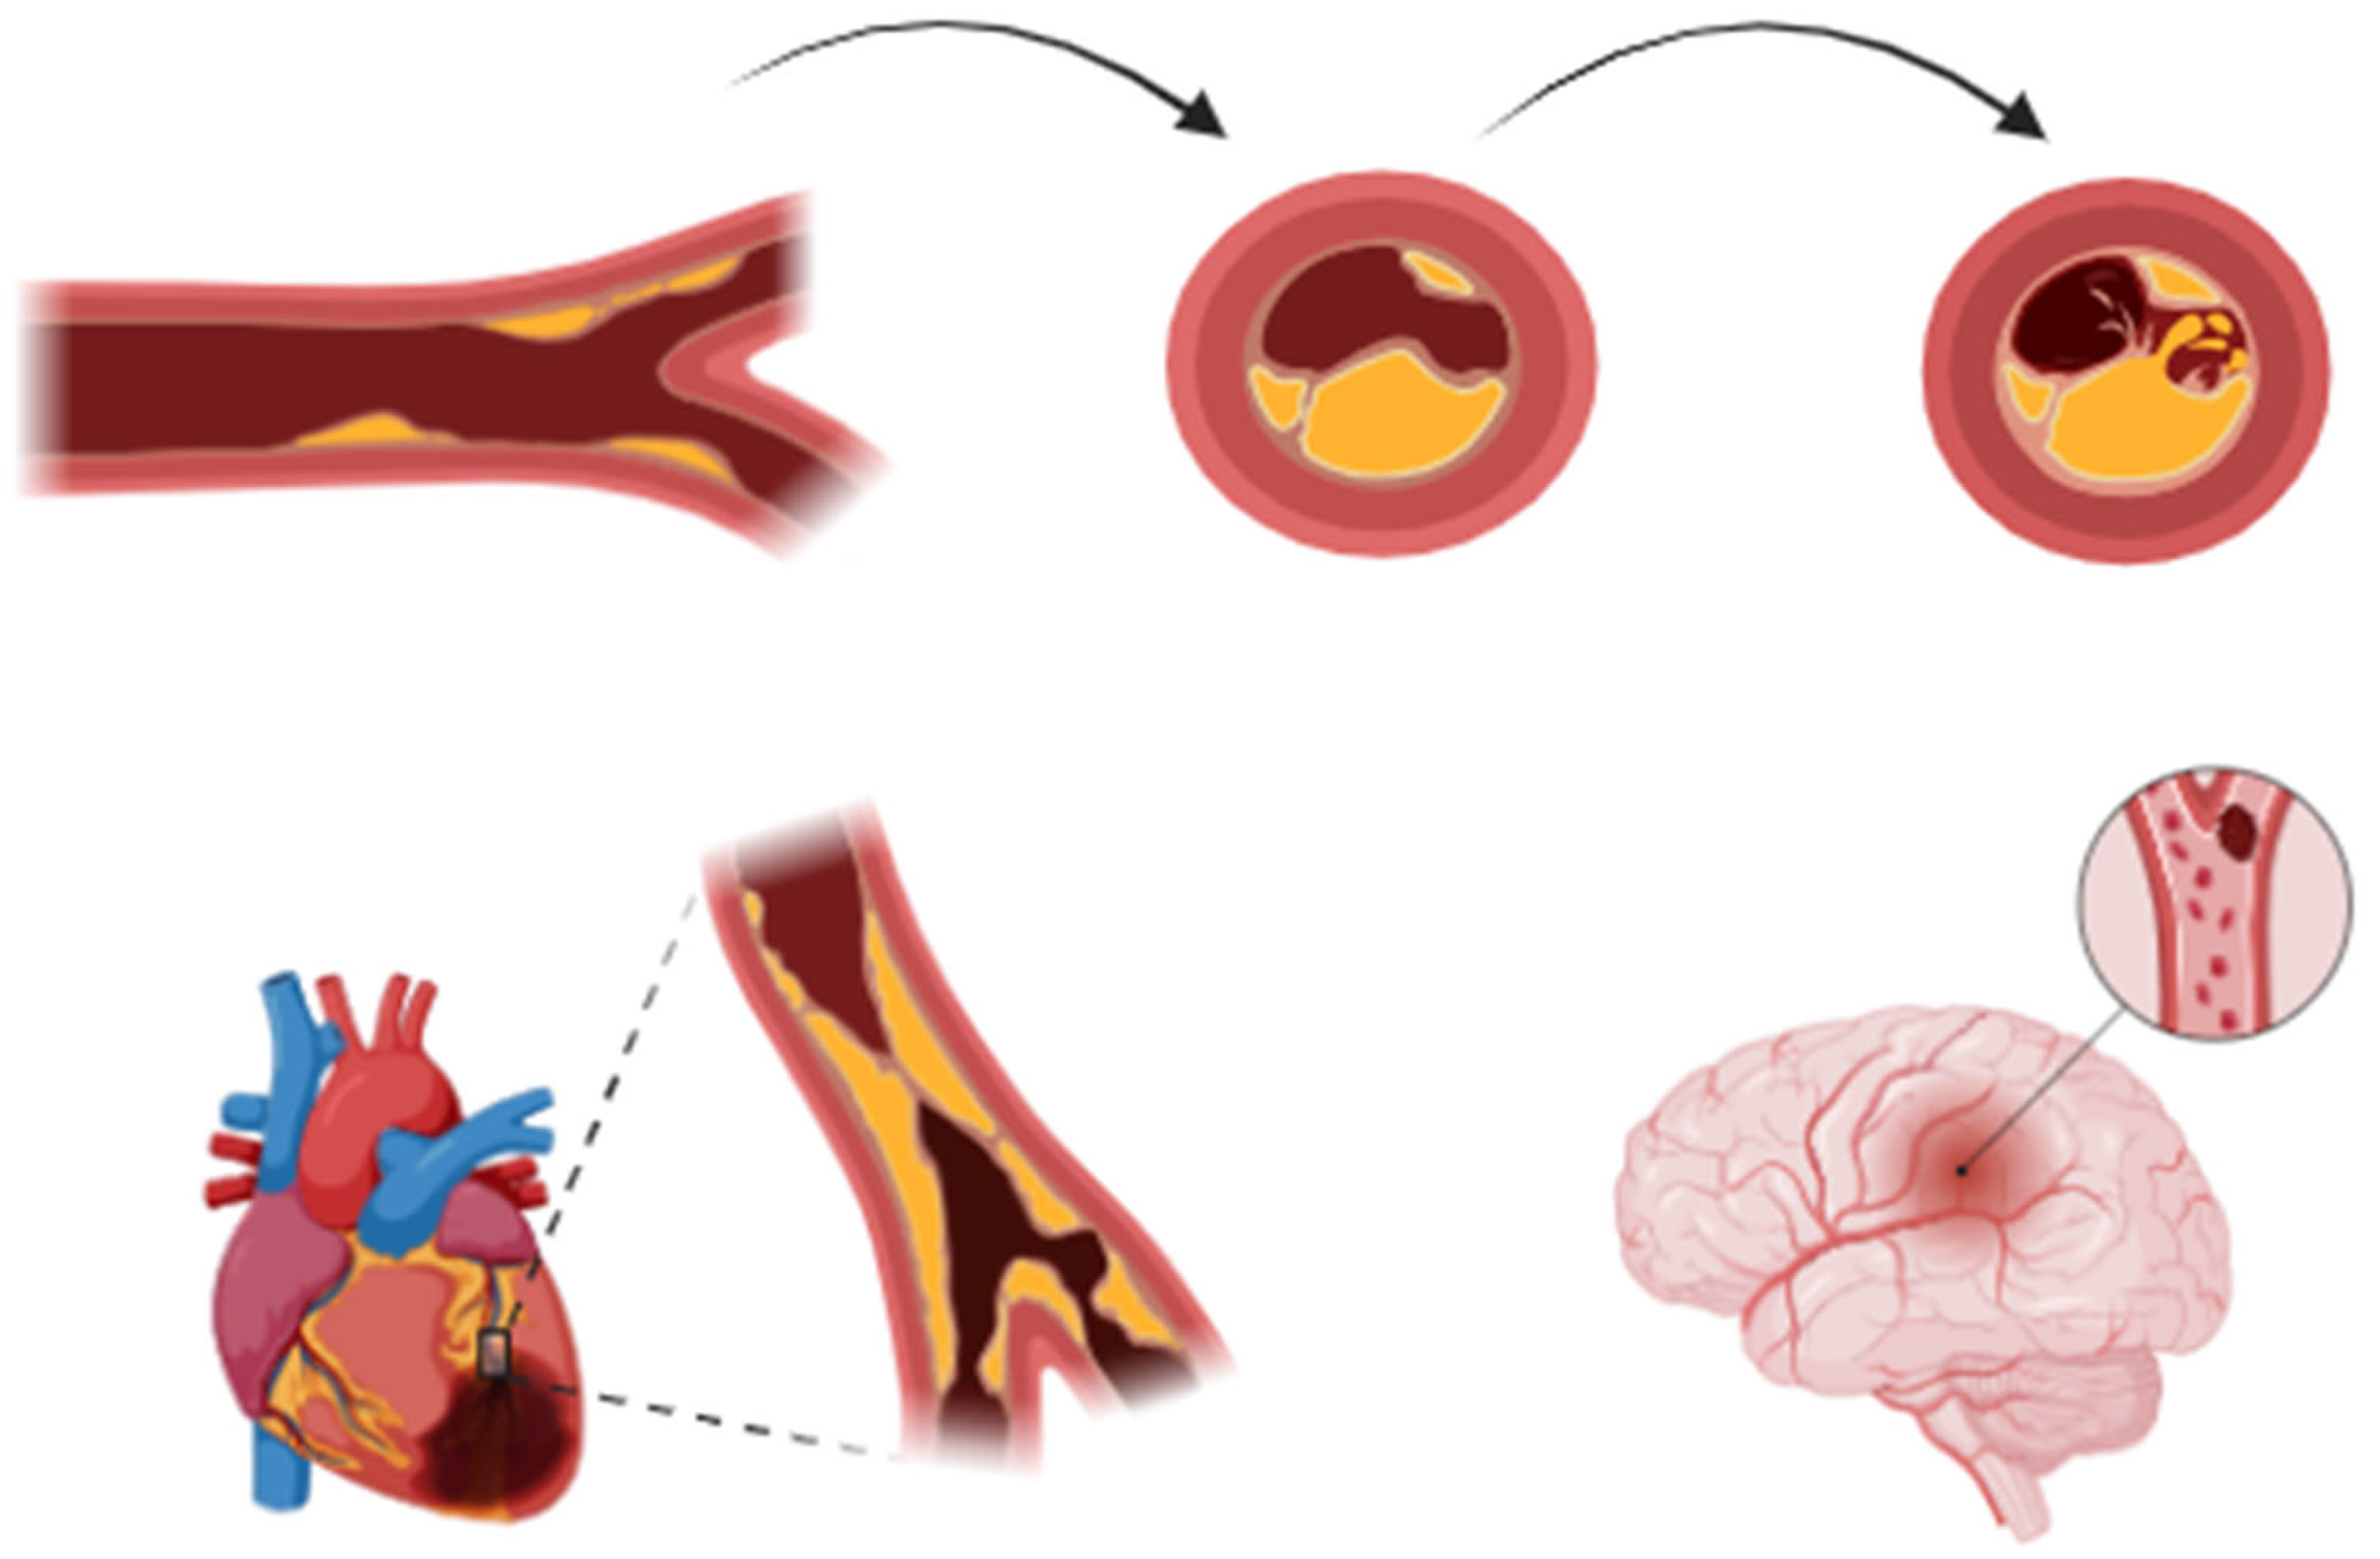

2. Pathophysiology of Acute Coronary Events and Stroke

2.3. Pathophysiological Mechanisms of Stroke in Acute Coronary Syndrome Patients

2.5. Cardioembolic Mechanisms and Procedural Risk in Ischemic Stroke Following Myocardial Infarction

2.6. Procedural Risks in Stroke Development